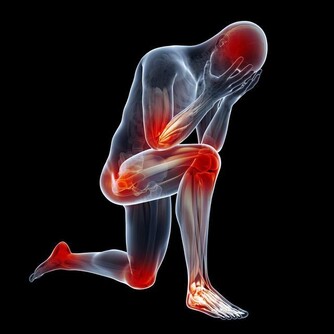

4、腰酸背痛、腰酸背痛不僅是男人出現的問題,女性也是經常有,尤其是到了一定的年齡階段,而這一癥狀的出現,人們也能很快的聯想到腎臟可能出現了問題。《素問。六節臟象論》中有說:「脊者....其充在骨」,說明骨髓的功能得以維持的能量來源於腎臟,骨髓由腎精所化生,《素問‧陰陽應像大論》中也強調:「腎主骨髓。」因為腎藏精,而精生骨髓,骨髓充實,骨骼強壯,運動捷健。所以說腎的精氣盛衰,直接影響骨骼的生長、營養、功能等。

所以腎氣衰敗很容易出現骨質疏鬆、腰酸背痛,甚至是牙齒出現鬆動等癥狀。